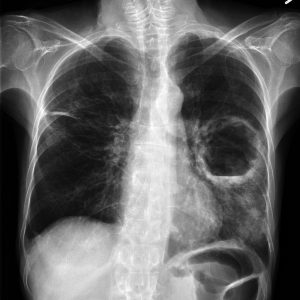

Ho gà ở trẻ sơ sinh (Pertusis) là một bệnh lý nhiễm trùng – nhiễm độc cấp tính đường hô hấp. Bệnh gây ra bởi vi khuẩn Bordetella pertussis. Triệu chứng thường gặp là các cơn ho dữ dội, mất kiểm soát, có thể dẫn tới khó thở, âm thanh thở rít. Ba mẹ thường […]